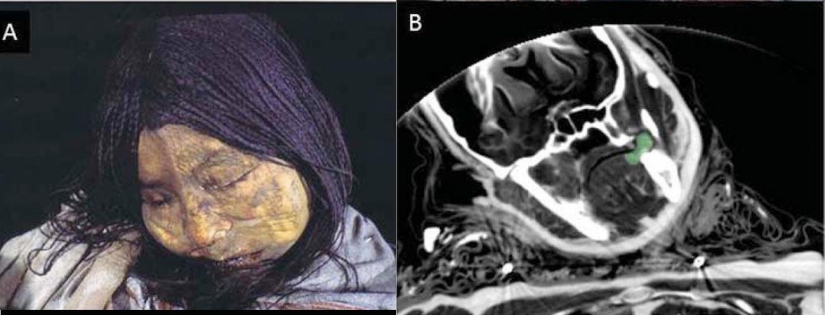

No hace mucho tiempo se supo que una misteriosa momia, que ha estado en la colección de un museo alemán durante más de un siglo, puede resultar ser una mujer inca que murió de varios golpes en la cabeza, probablemente durante un asesinato ritual.

En la cabeza de la momia había bandas elásticas hechas de lana de alpaca y llama. Esto podría indicar que la momia viene de América del Sur.

Su cráneo también tenía los característicos huesos "wormianos", que solo se encuentran en los pueblos sudamericanos, pero no en los europeos.

Por un lado, la cara de la momia parecía bastante normal, pero dentro de sus huesos del cráneo estaban rotos.

Como puedes ver, la parte frontal de su cráneo está completamente aplastada.

Las exploraciones también mostraron signos de una pared cardíaca compacta e intestinos hinchados. Lo más probable es que fuera causada por la enfermedad de Chagas.

Rayos X del cuerpo de la momia Inca.